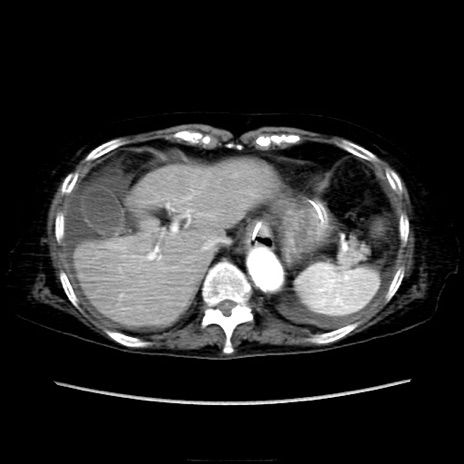

症例40(横断像)

横断像